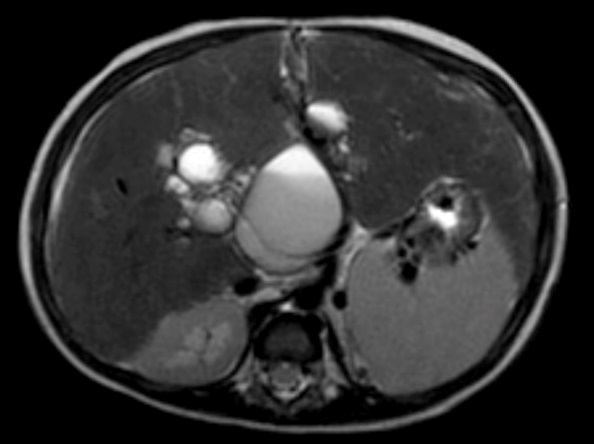

Upper gastrointestinal endoscopy (Figure 4) demonstrated the presence of grade 3-4 gastroesophageal varices, from corpus gastric proximally to the four columns of esophagus without active bleeding. Gastric mucosa was hyperemic, which indicate gastropathy. Ligation was done twice, two months apart.

Figure 4: Upper gastrointestinal endoscopic.